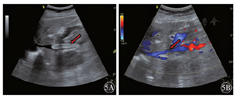

患者1女性,35岁。因"反复双下肢浮肿3个月"于2018年10月19日入院。入院后于2018年10月23日行彩色多普勒超声检查提示下腔静脉近段血流充盈缺损,管腔内为不规则、实质性、混合回声填充并黏附管腔后壁,狭窄率为60%~70%,长约3.0 cm,血栓基底部未见明显血流进入(图1)。右肾静脉无血流信号显示。2018年10月29日复查彩超检查显示下腔静脉近段管腔内混合回声团块上端漂浮,血流冲击基底部,基底部黏附于下腔静脉后壁,血流充盈缺损,狭窄率50%~60%,狭窄段长约3.0~4.0 cm,右肾静脉血流通畅(图2)。为防止血栓脱落导致肺栓塞,于2018年10月30日行下腔静脉滤器置入术,术后患者病情稳定并进一步行下腔静脉置管溶栓术。彩超检查提示下腔静脉内可见溶栓导管,管腔内仍可见不规则、实质性、混合回声填充,血流不规则充盈缺损。混合回声团块上端未见明显漂浮,无明显血流信号进入基底部(图3)。置管溶栓过程中,下腔静脉内仍可见部分附壁血栓黏附,于2018年11月19日行下腔静脉切开取栓、滤器取出术,术中见滤器有小块血栓附着,夹出下腔静脉壁上血栓,部分血栓与下腔静脉后壁黏附紧密,仔细剥离至取栓满意。术后患者生命体征平稳。术后病理诊断:下腔静脉混合血栓。行彩超检查提示下腔静脉内血流通畅,充盈良好,双肾静脉血流通畅(图4)。患者于2019年12月1日出院。